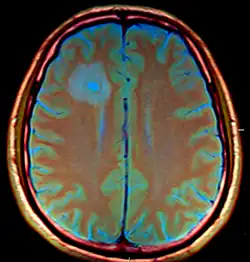

Brain abscess after metastasis treatment.

Anaerobic and microaerophilic cocci and gram-negative and gram-positive anaerobic bacilli are the predominant bacterial isolates. Many brain abscesses are polymicrobial. The predominant organisms include: Staphylococcus aureus, aerobic and anaerobic streptococci (especially Streptococcus intermedius), Bacteroides, Prevotella, and Fusobacterium species, Enterobacteriaceae, Pseudomonas species, and other anaerobes.[6] Less common organisms include: Haemophillus influenzae, Streptococcus pneumoniae and Neisseria meningitidis.[7]